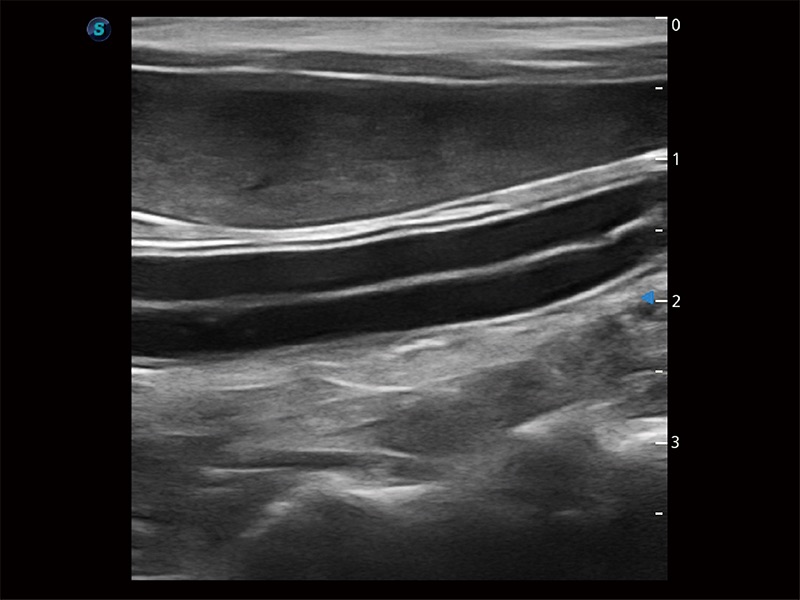

操作简便,无需高频度外力作用即可真实反映组织的形变,快速评估肿瘤良恶性。

为精细结构及组织边缘提供高清晰度的图像和更大的成像视野。帮助减轻医生的用眼疲劳,快速精准获得测量的数据。

ProPet 80 全新的动物超声智能软件和丰富的探头群,为动物医生提供了高清晰度和精细分辨率的图像,无论在宠物、马科、畜牧还是实验室动物等应用中都可以轻松应对,为您的日常工作带来满意的体验。